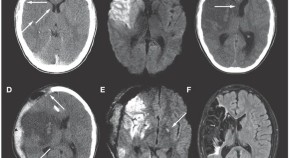

In this month's Case Study, Satoda et al. describe a patient who presented with an acute myocardial infarction 5 weeks after giving birth. Angiography revealed a severe diffuse lesion of the left anterior descending artery, which was later confirmed to be a spiral dissection. The lesion resolved after two months of medical therapy, and the patient recovered well.